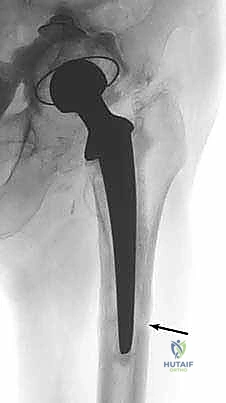

Radiographs from patients with long-standing chronic infection will show signs of deep infection. A periosteal reaction is considered pathognomonic for deep infection. Sinus tracks, extending through bone, may rarely be seen (FIG 2).

Illustration 6 for Resection Arthroplasty & Spacers: Optimizing Time of Reimplantation FIG 2 A. Anteroposterior (AP) radiograph of infected total hip replacement showing a sinus tract through the lateral cortex (arrow). B. AP radiograph of infected total hip replacement showing periosteal reaction (black arrows) and sinus tract (white arrow) through posteromedial cortex.

Varus remodeling of the proximal femur, or cement that is wider distally than proximally and still well fixed to the implant within the canal, impedes removal of the femoral component and increases the risk of fracture (FIG 3).

FIG 3 • AP radiograph of loose femoral component. The stem has failed at the bone-cement interface and the

cement is still well fixed to the implant. Removal from above would be difficult as the cement becomes wider in the metaphyseal region (white arrows). An extended trochanteric osteotomy is required to remove the stem safely.